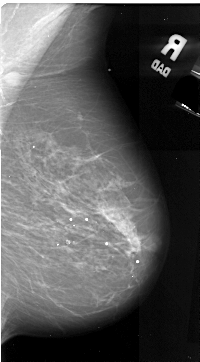

A_1049_1.RIGHT_MLO

RIGHT_CC LINES 5146 PIXELS_PER_LINE 2716 BITS_PER_PIXEL 16 RESOLUTION 42 NON_OVERLAY

RIGHT_MLO LINES 5416 PIXELS_PER_LINE 2986 BITS_PER_PIXEL 16 RESOLUTION 42 NON_OVERLAY